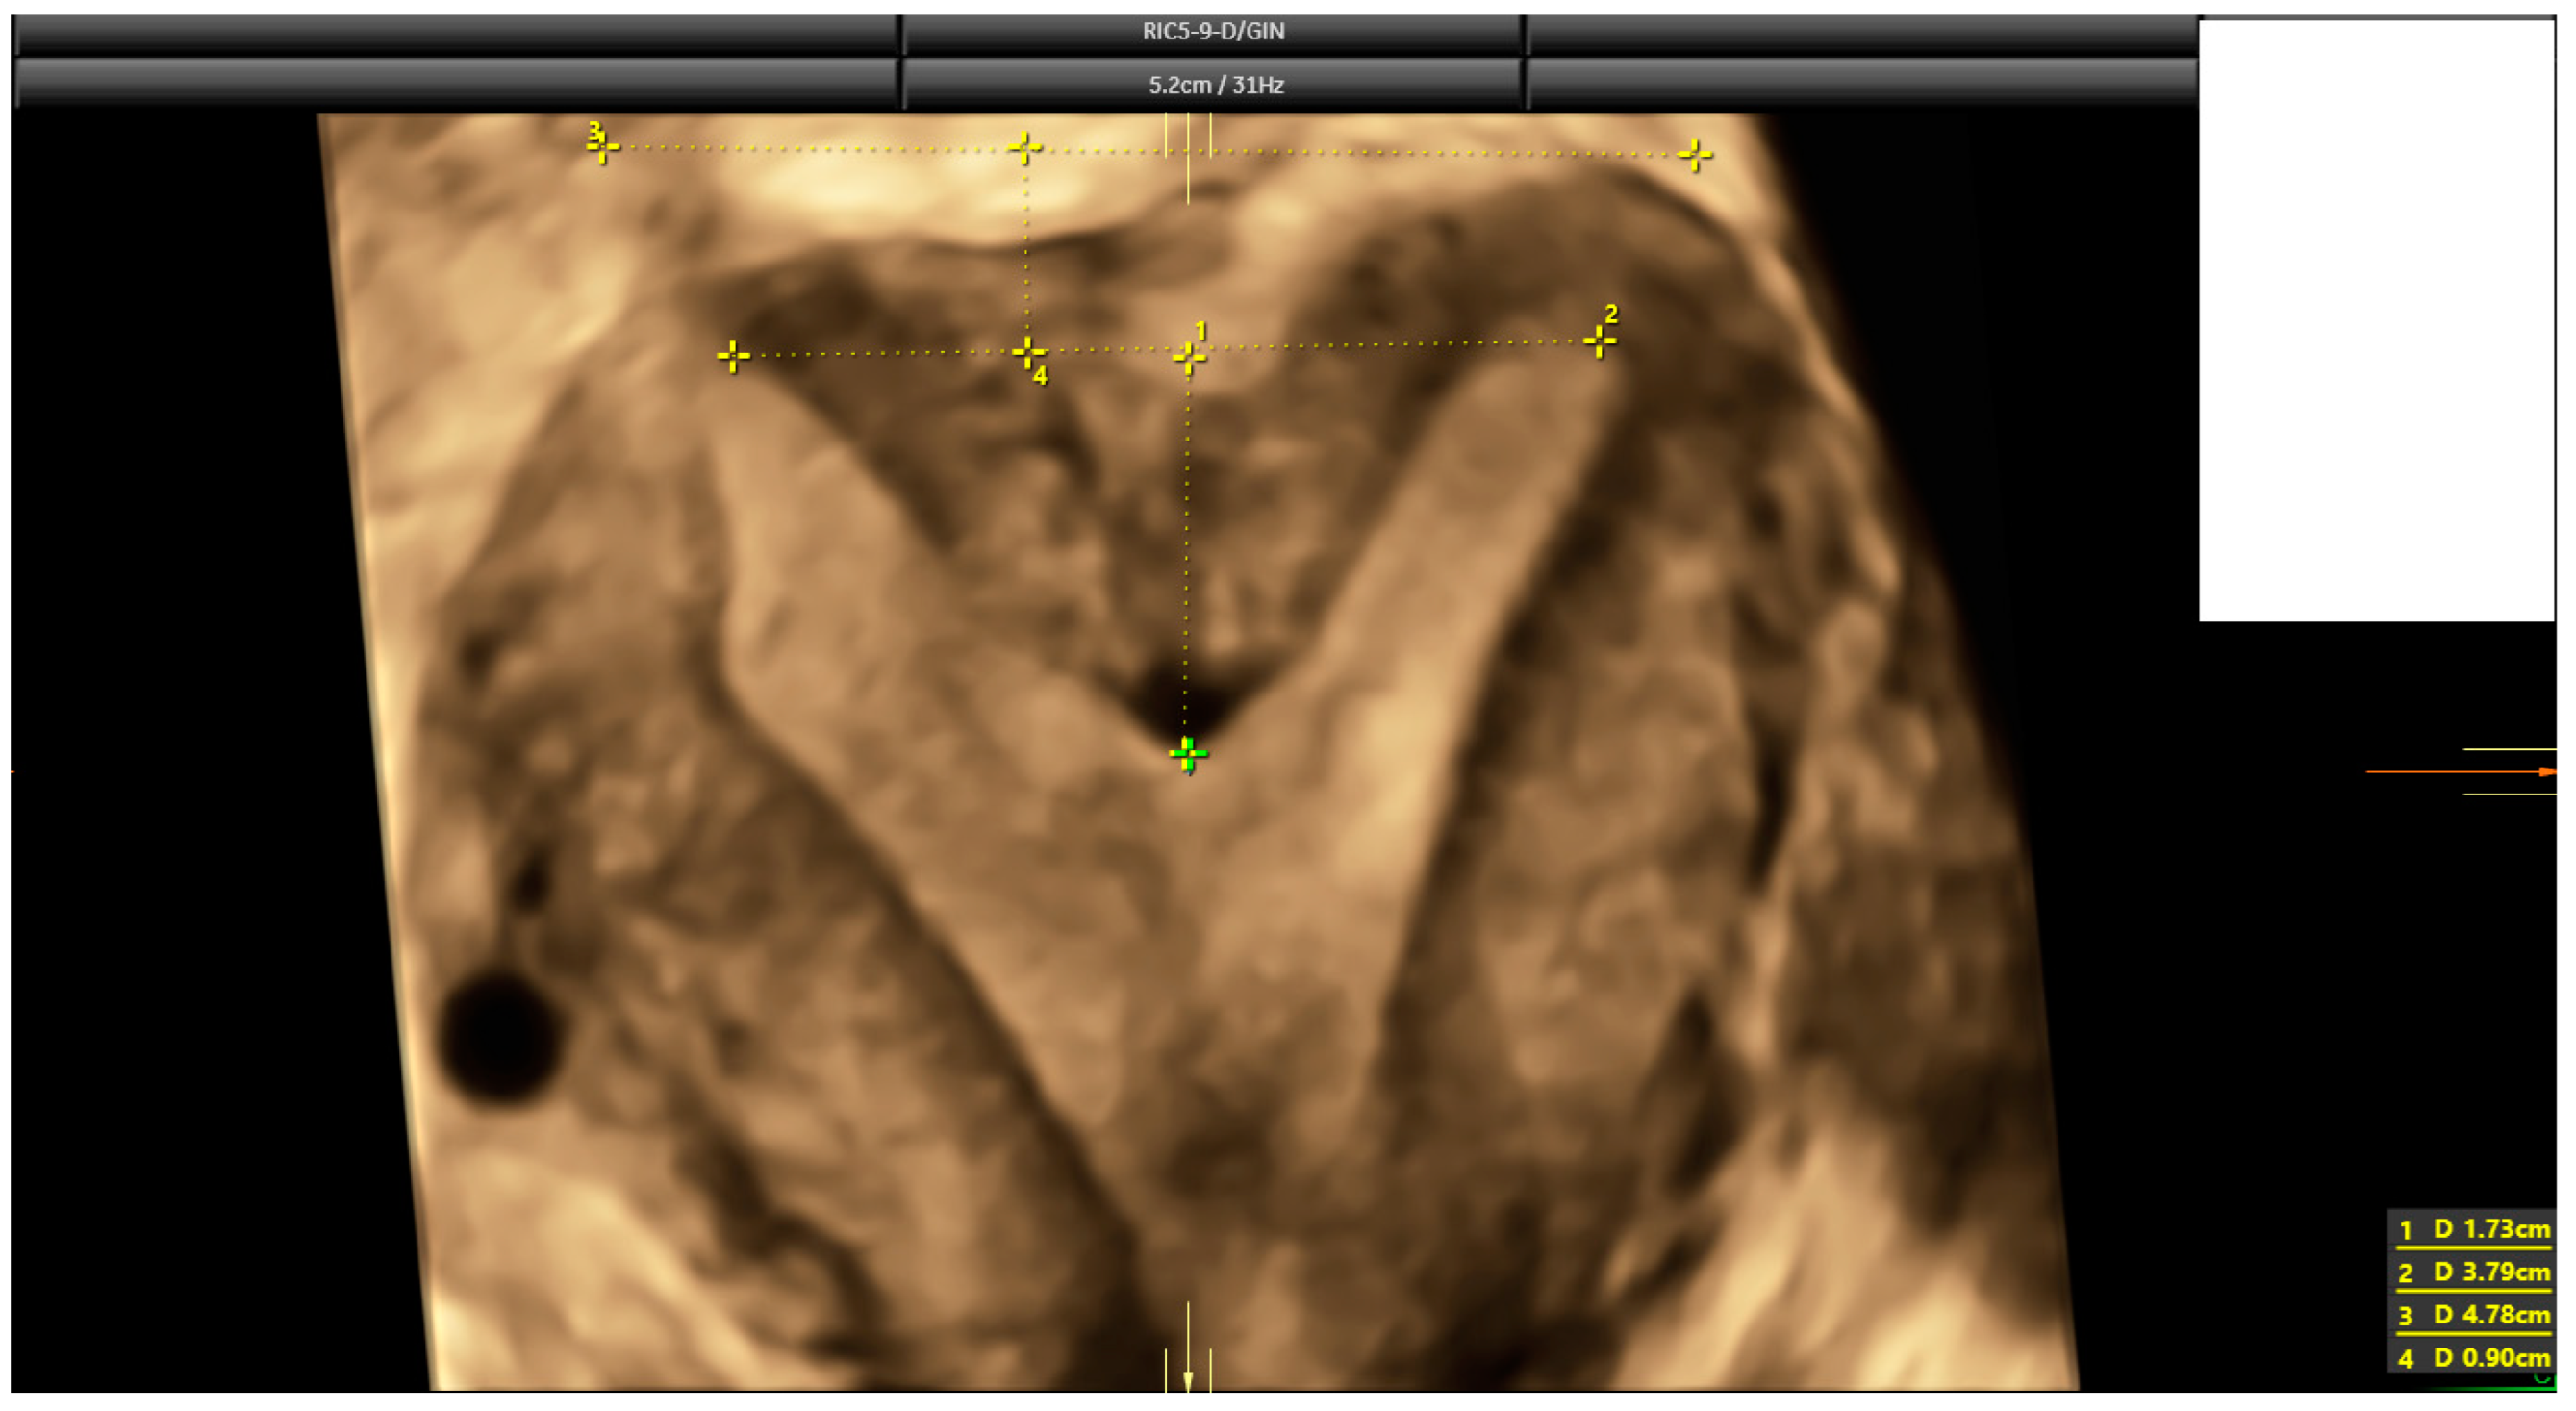

2.3. Ultrasound Evaluation

- Ludwin, A.; Martins, W.P. Correct measurements of uterine fundal internal indentation depth and angle: An important but overlooked issue for precise diagnosis of uterine anomalies. Ultrasound Obstet. Gynecol. 2021, 58, 497–499. [Google Scholar] [CrossRef] [PubMed]

| Indentation length * | 2.0 mm (2.3) | Range: 0–37 mm |

| Uterine Wall thickness * | 10.0 mm (3.7) | Range: 3.3–26.0 mm |

| Indentation angle * | 169° (21.0) | Range: 0–180° |

| I:WT ratio * | 20% (27.0) | Range: 1–596% |